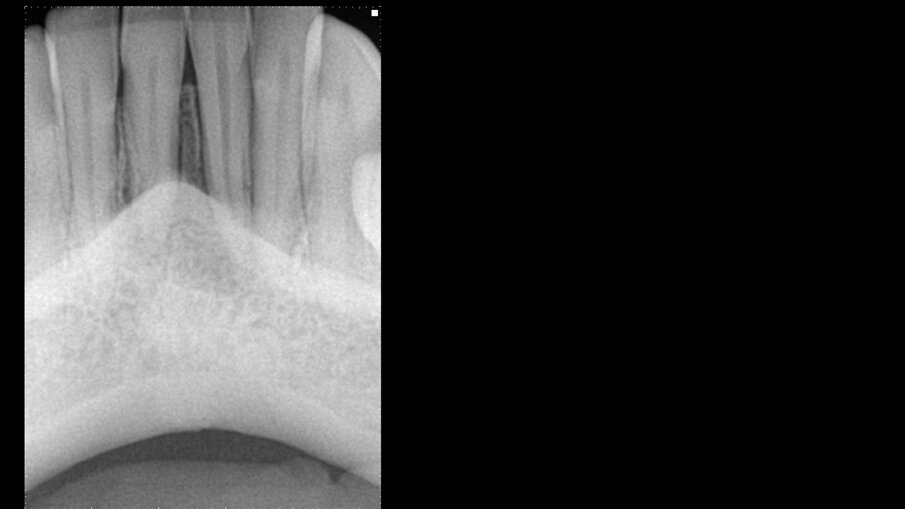

Slika 1: Radiografija pacijentkinje pre operacije.

Mlada pacijentkinja, manekenka kojoj je mnogo stalo do njenog izgleda i želi da izgleda prirodno, došla je u našu ordinaciju sa otokom donje vilice ispod dva centralna sekutića. Po konsultaciji sa našim parodontologom i protetičarom, džep širine preko 20 mm, koji se prostire od jednog centralnog sekutića do drugog, otkriven je, ukazujući da je cela kortikalna ploča nestala. Ovo, zajedno sa Klasom III pokretljivosti oba centralna sekutića, bila je „crvena zastavica“ za parodontologa. U testiranju vitalnosti zuba, dva centralna sekutića nisu reagovala na hladni test dok su preostali zubi bili normalni. Na rendgenskom snimku problem nije bio vidljiv (slika 1). I-CAT skeniranje je napravljeno da bi se bolje razumeo problem. Skeniranje je prikazalo horizontalni i vertikalni pogled na leziju. Horizontalni pogled je pokazao gubitak i kortikalne i trabekularne kosti od levog centralnog sekutića do desnog bočnog sekutića, ukupne dužine skoro 14,11 mm i dubinom od 6,28 mm (slika 2a). Vertikalni pogled nam je pokazao da nema kosti na bukalnom aspektu i da nema kosti ispod centralnih sekutića skoro do nivoa vrha zub (slike 2b i c). Došlo je i do horizontalnog gubitka kosti od 5,5 mm do 6,3 mm. Ovo je bila situacija koja se često smatrala beznadežnom, a spasavanje ovih zuba izgledalo je nemoguće.